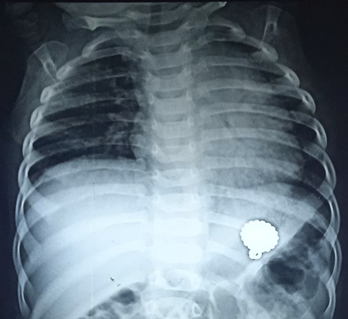

Age distribution of patients shown in Table 1, Foreign body was commonly seen 22 (75.9%) in 1-5 years of age, as shown in Table 1. Table 2 shows sex distribution of foreign body ingestion cases, where 15 (51.7%) were male child. Among the ingested foreign bodies only 3 (10.3%) were removed within 24 hours of ingestion, 10 (34.5%) cases were removed between 24-48 hours and the remaining 16 (55.2%) were removed after 48 hours (Table 3). Coin was the most commonly ingested foreign body 19 (65.5%). Other foreign bodies were metallic chain 3 (10.3%), button battery 2 (6.9%), others 5 (17.2%), (Figure 1 - Figure 3). Most of the ingested foreign bodies were found in the stomach, few were in upper esophagus (Table 4). There were no complications either during endoscopy or after foreign body removal.

Figure 1 Various ingested foreign bodies removed by using Olympus CV-150 model endoscopy.

Figure 3 X-ray chest showing foreign body in stomach of a 2-year-old child.